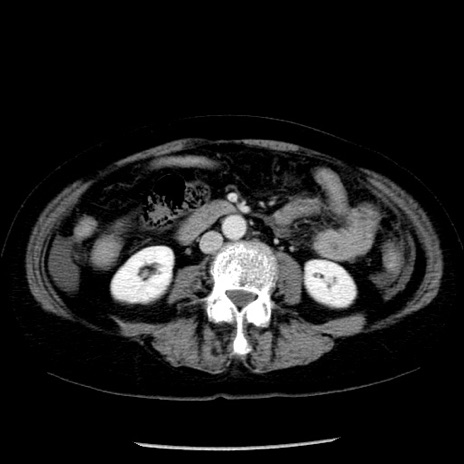

症例13(横断像)

【症例】70歳代女性

【主訴】腹痛、嘔吐

【現病歴】15時間程前(昨晩)より腹痛あり。今朝になっても症状の改善なく、嘔吐あり。腹痛も増悪あり、救急外来受診。

【既往歴】子宮癌全摘術後

【身体所見】意識清明、BP 121/72mmHg、P 74bpm、SpO2 100%(RA)、腹部:平坦・軟、腸雑音ほぼ聴取せず。下腹部・心窩部・臍左上に圧痛あり。反跳痛なし。

【データ】WBC 10600、CRP 0.15